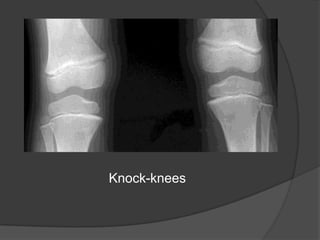

Knock-knees(genuvalgum) in older children

Valgus or varus deformities